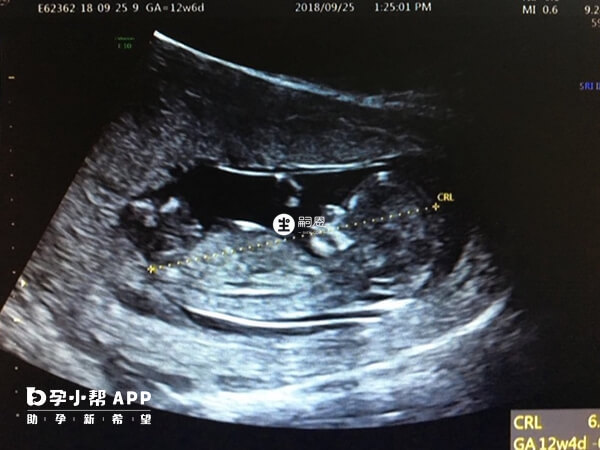

我老婆目前懷孕11周+2,再過幾天12周的時候就要去做nt檢查了。聽別人說做nt檢查,B超報告單上面的一些資訊資料可以看出是男寶還是女寶,說是有特點的。還聽說nt照,寶寶尾骨往上翹的是男寶,比較平的是女寶,請問這個看法準嗎?尾骨上翹一定是男孩的特點嗎?在懷孕12周做nt檢查的時候,可以通過nt單子上面的nt值,或者是胎兒的胎心率,以及雙頂徑等其他描述,可能看出男寶的特點。但其實nt看男女這個並沒有科學依據,各位寶媽也不必太在意了。如果發現胎兒尾骨上翹,是男寶的特點可能性大。也有一種說法就是胎兒的特徵點與軀體成45度角,那麼懷男寶的可能性大。如果胎兒的特徵點與軀體平行,就是懷女寶的可能性大。這種看法的解釋是說胎兒屁股位置微微上翹,後背脊柱成圓弧狀,是為了給前列腺留髮育空間。

除此之外,nt看男女的說法也還有看nt值,NT值大於1.5的寶寶就是男孩,而小於1.5就是女孩。另一個就是看B超影象,如果是女寶寶,nt超圖可以看到三條線,兩腿中間有小凹槽,那是女孩的小陰脣。如果是男寶寶,nt超圖可以看到亮點,兩腿中間有小突起,屁股也是向上翹的。

孕期NT檢查可以檢測胎兒頸部的透明帶厚度和鼻骨是否正常,從而評估胎兒是否有患唐氏綜合徵等染色體異常的風險。同時,有些人認為通過NT檢查的圖片可以預測胎兒的性別。特此對於NT圖看男女進行了相關整理,有需要的可以瞭解一下。